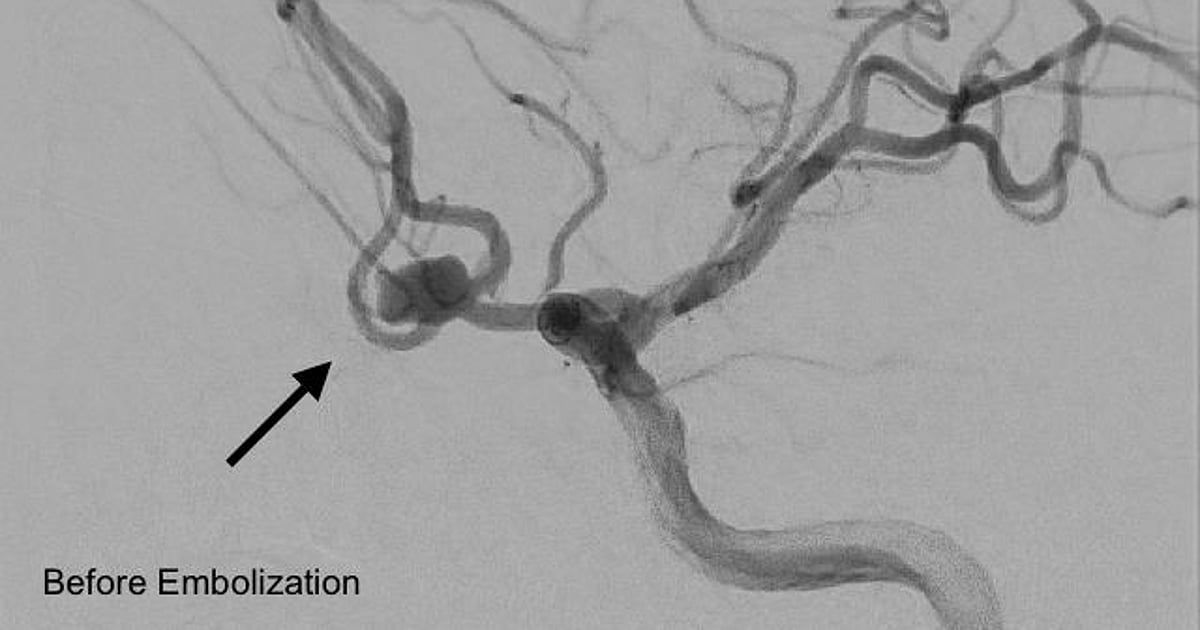

حقق مستشفى المانع بالأحساء إنجازًا طبيًا بنجاح تنفيذ أول إجراء من نوعه لإغلاق تمدد شرياني دماغي نازف بالقسطرة لمريض يبلغ من العمر 45 عامًا، جرى تحويله من مستشفى آخر إثر إصابته بنزيف حاد في الدماغ.

ونُفِّذ الإجراء بواسطة فريق التدخلات العصبية باستخدام ملفات معدنية دقيقة لإغلاق التمدد الشرياني، ما أسهم في السيطرة الكاملة على النزيف واستقرار حالة المريض واستعادته وعيه بالكامل.